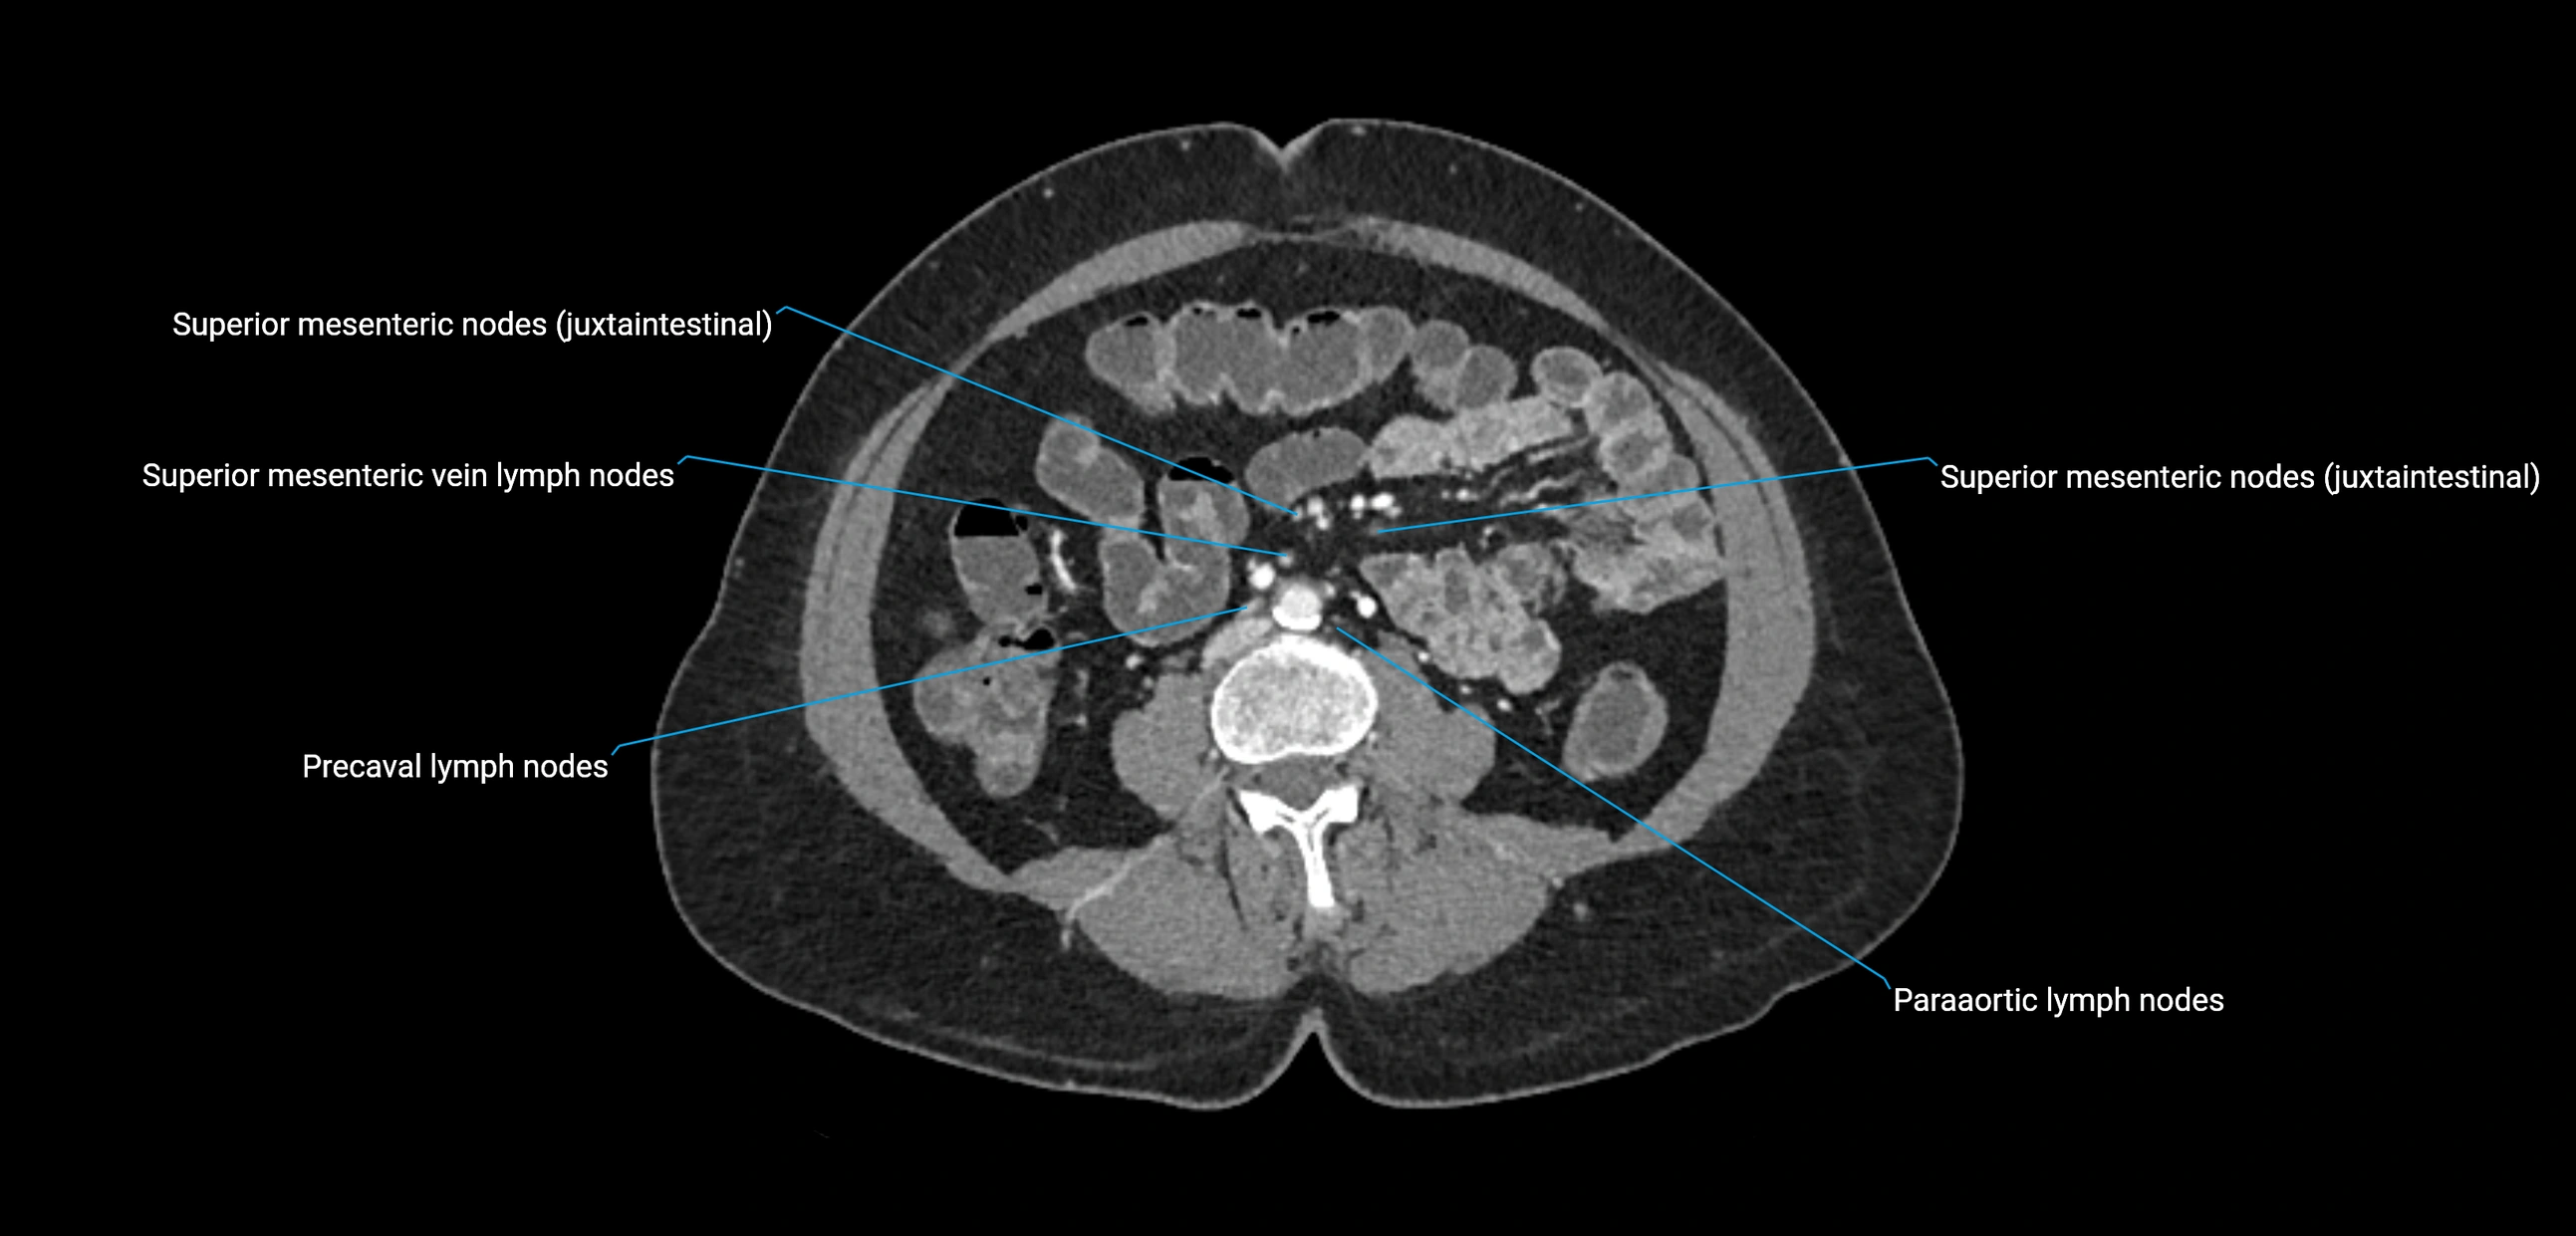

CT Appearance

CT Pre-Contrast:

• Nodes appear as soft-tissue density nodules adjacent to the aorta and IVC

• Calcification may be seen in chronic infections (e.g., tuberculosis)

CT Post-Contrast:

• Normal nodes enhance homogeneously

• Malignant nodes may show heterogeneous enhancement, central necrosis, or conglomerate formation

• Size >1 cm short axis is suspicious, though morphology and distribution are equally important